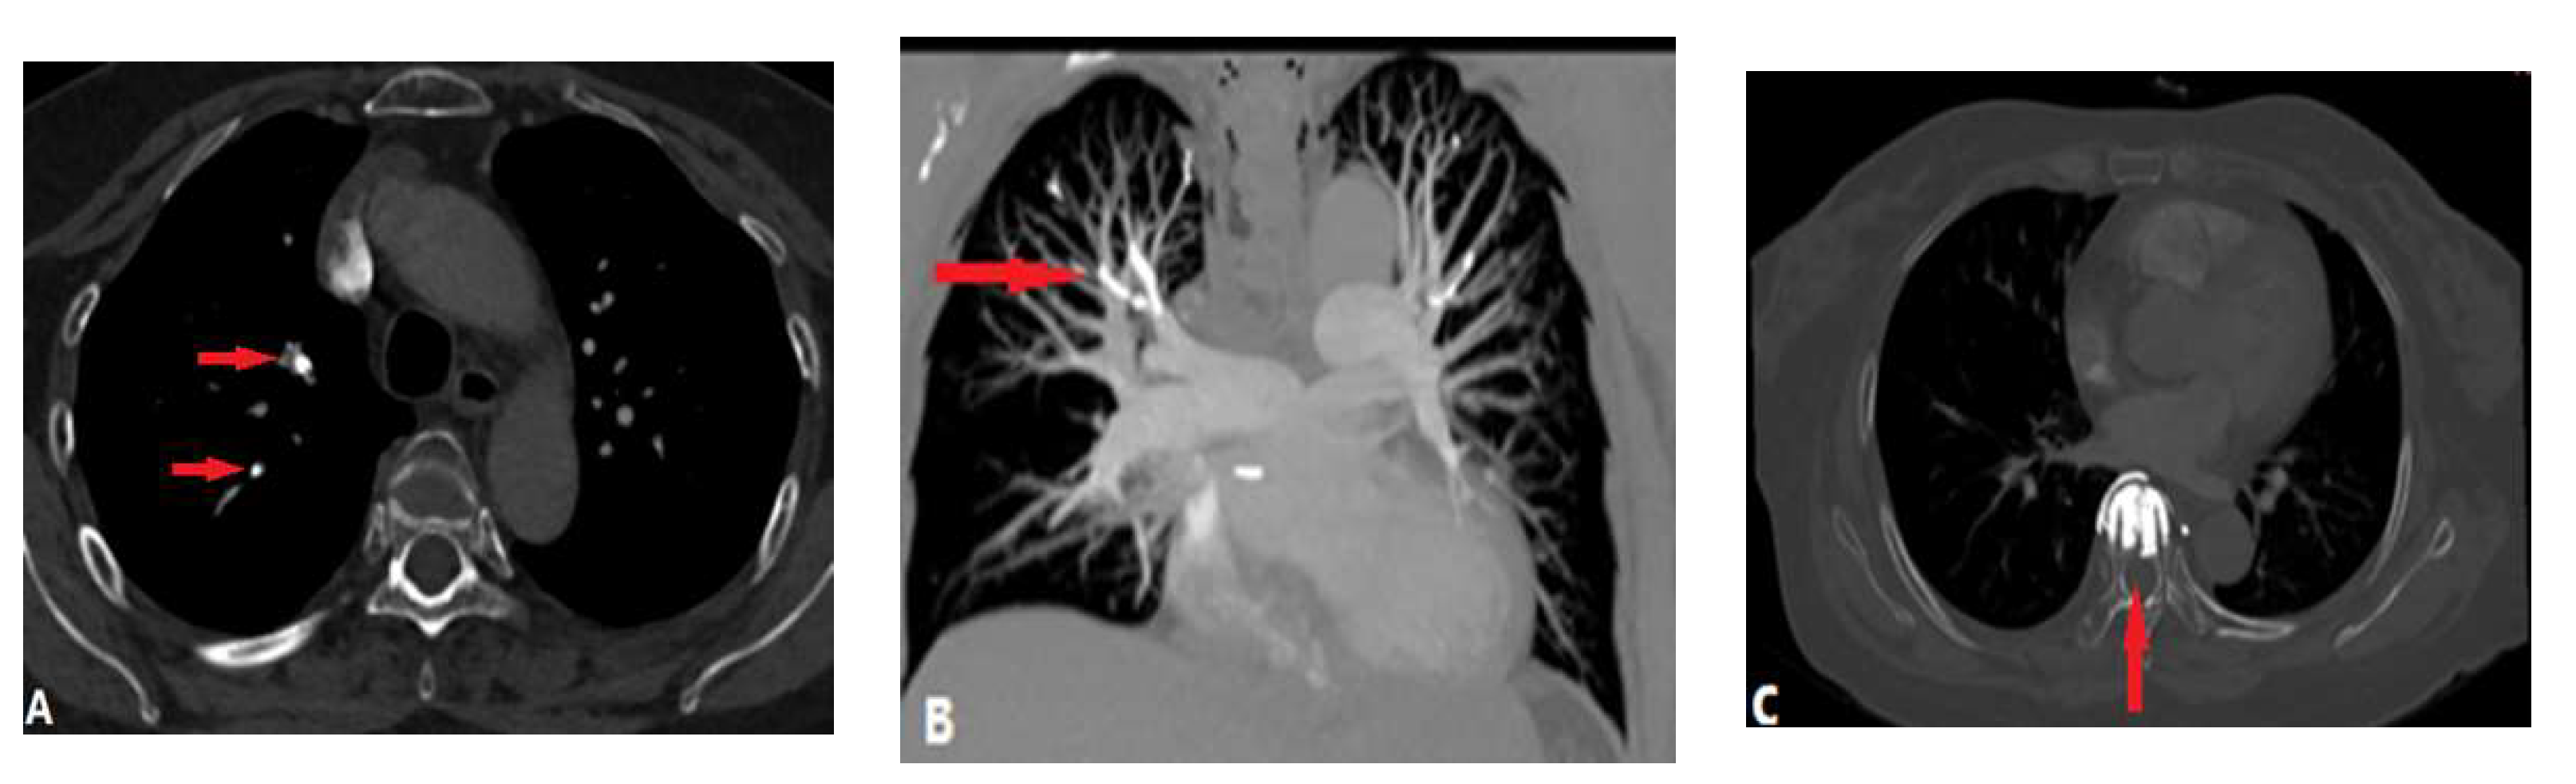

3.1.4. Septic Pulmonary Embolism (SPE)

3.1.5. Pulmonary Embolism caused by Foreign Bodies